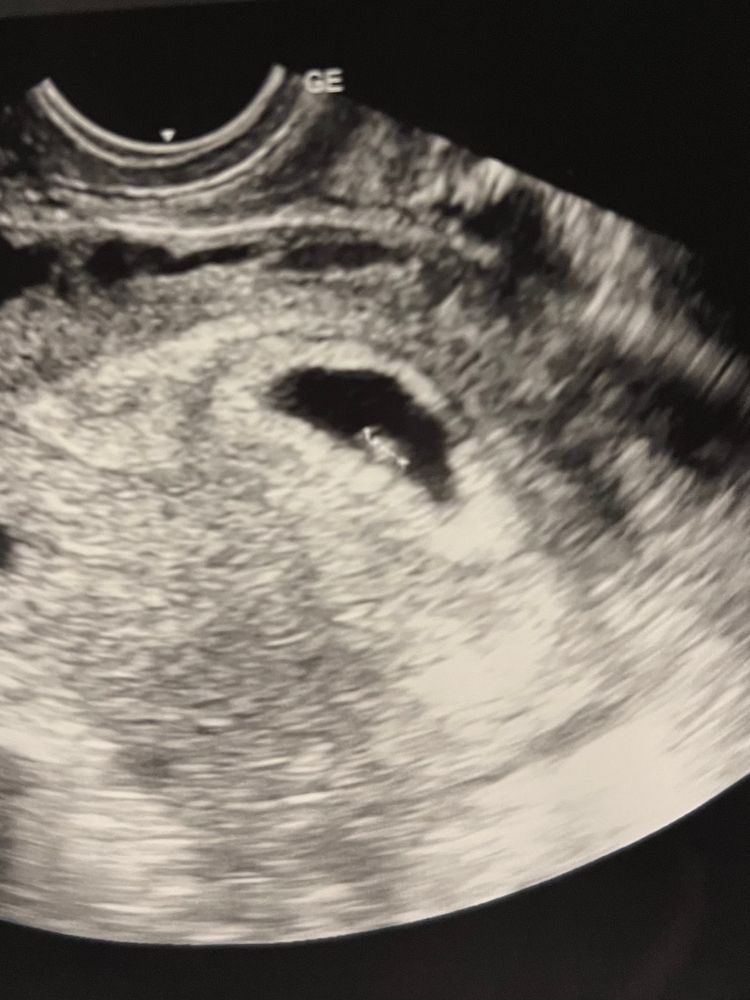

6 недель 3 дня. Нашли эмбрион и сердечко ❤️

Сегодня вечером планировалось первое узи, но днем увидела розовые выделения, поэтому экстренно поехала в больницу (накрутила себе уже всего самого страшного). К счастью, нашли эмбрион и послушала сердечко 🥰 Ни отслоек, ни гематом 🙏🏻

но мне кажется маловат ктр для такого срока - 3 мм (соответствует 5нед 4дн). Девочки, у кого тоже был маленький ктр? Дальше как развивалось?